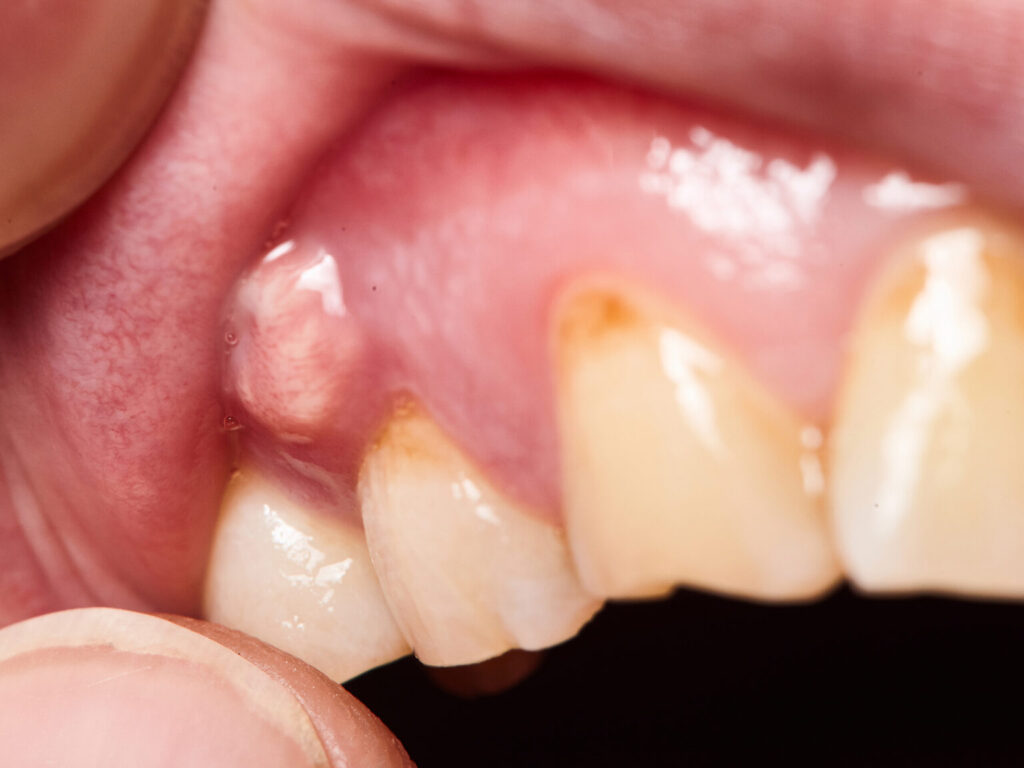

In more severe cases, individuals may experience fever, swollen lymph nodes in the neck or jaw, or difficulty opening the mouth. Sometimes, a visible bump or pimple-like swelling appears on the gum, which may rupture and release pus. While this might provide temporary relief, it does not mean the infection has healed. All symptoms of an abscess, whether mild or severe, warrant professional evaluation to prevent the spread of infection and systemic complications.